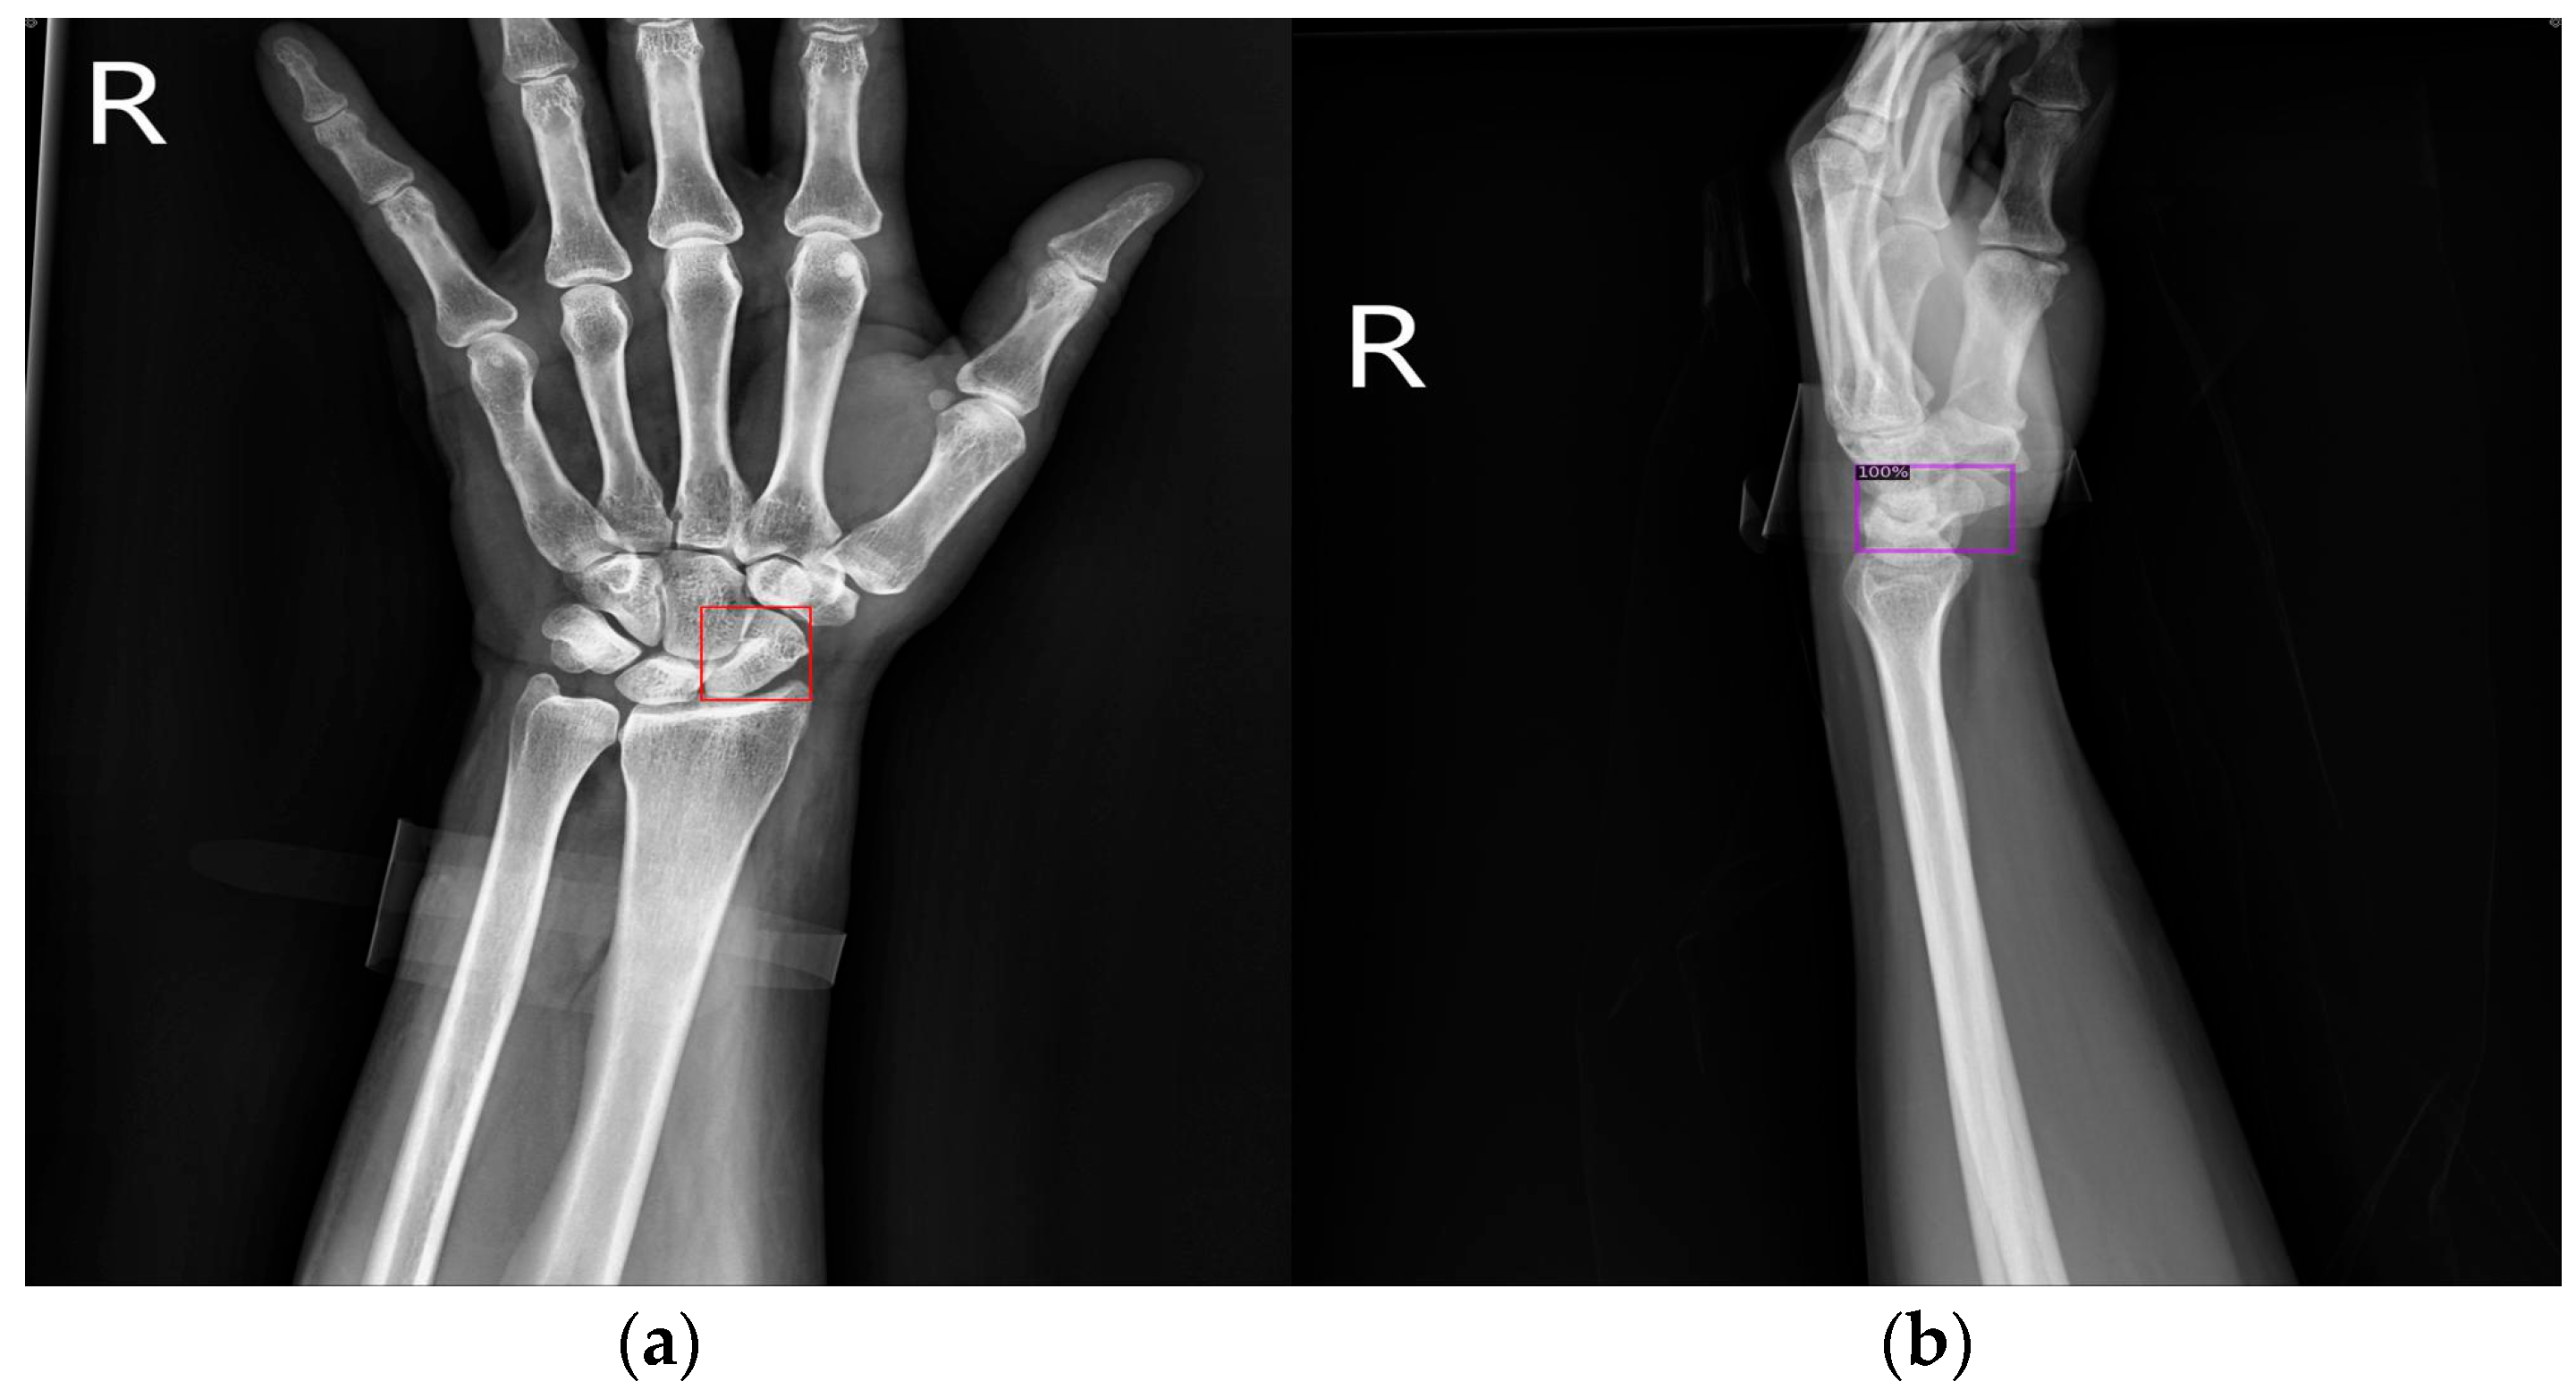

Figure 9 shows the results of scaphoid fracture detection. In the figure, the red area represents the ground-truth box labeled by the doctor, while the green area shows the result predicted by the model. Figure 10 provides an example of a more obvious fracture, whereas Figure 11 illustrates an example of an occult fracture. These examples highlight the challenges in diagnosing scaphoid fractures, as occult fractures are difficult to distinguish by the naked eye. The AP views demonstrate a relatively high IoU, while the LA views also accurately locate the fracture area. This combined approach is effective in drawing the doctor’s attention to the area, enabling quicker identification of the fracture location.

Figure 9.

Scaphoid detection visualization. (a–d) The AP and LA views of the same patient. The first row is the ground truth, and the second row is the predicted result.

Figure 10.

Fracture detection visualization. (a,b) Scaphoid bone slices. The red box is the true answer, and the green box is the predicted result.